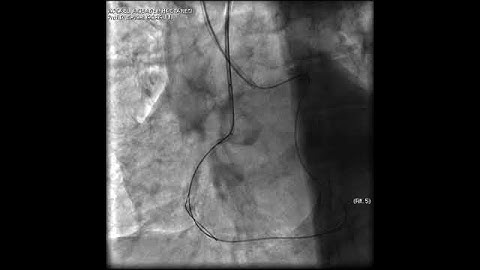

Aortic dissection and radial rupture during retrograde CTO PCI: Management of complications VİDEO 15